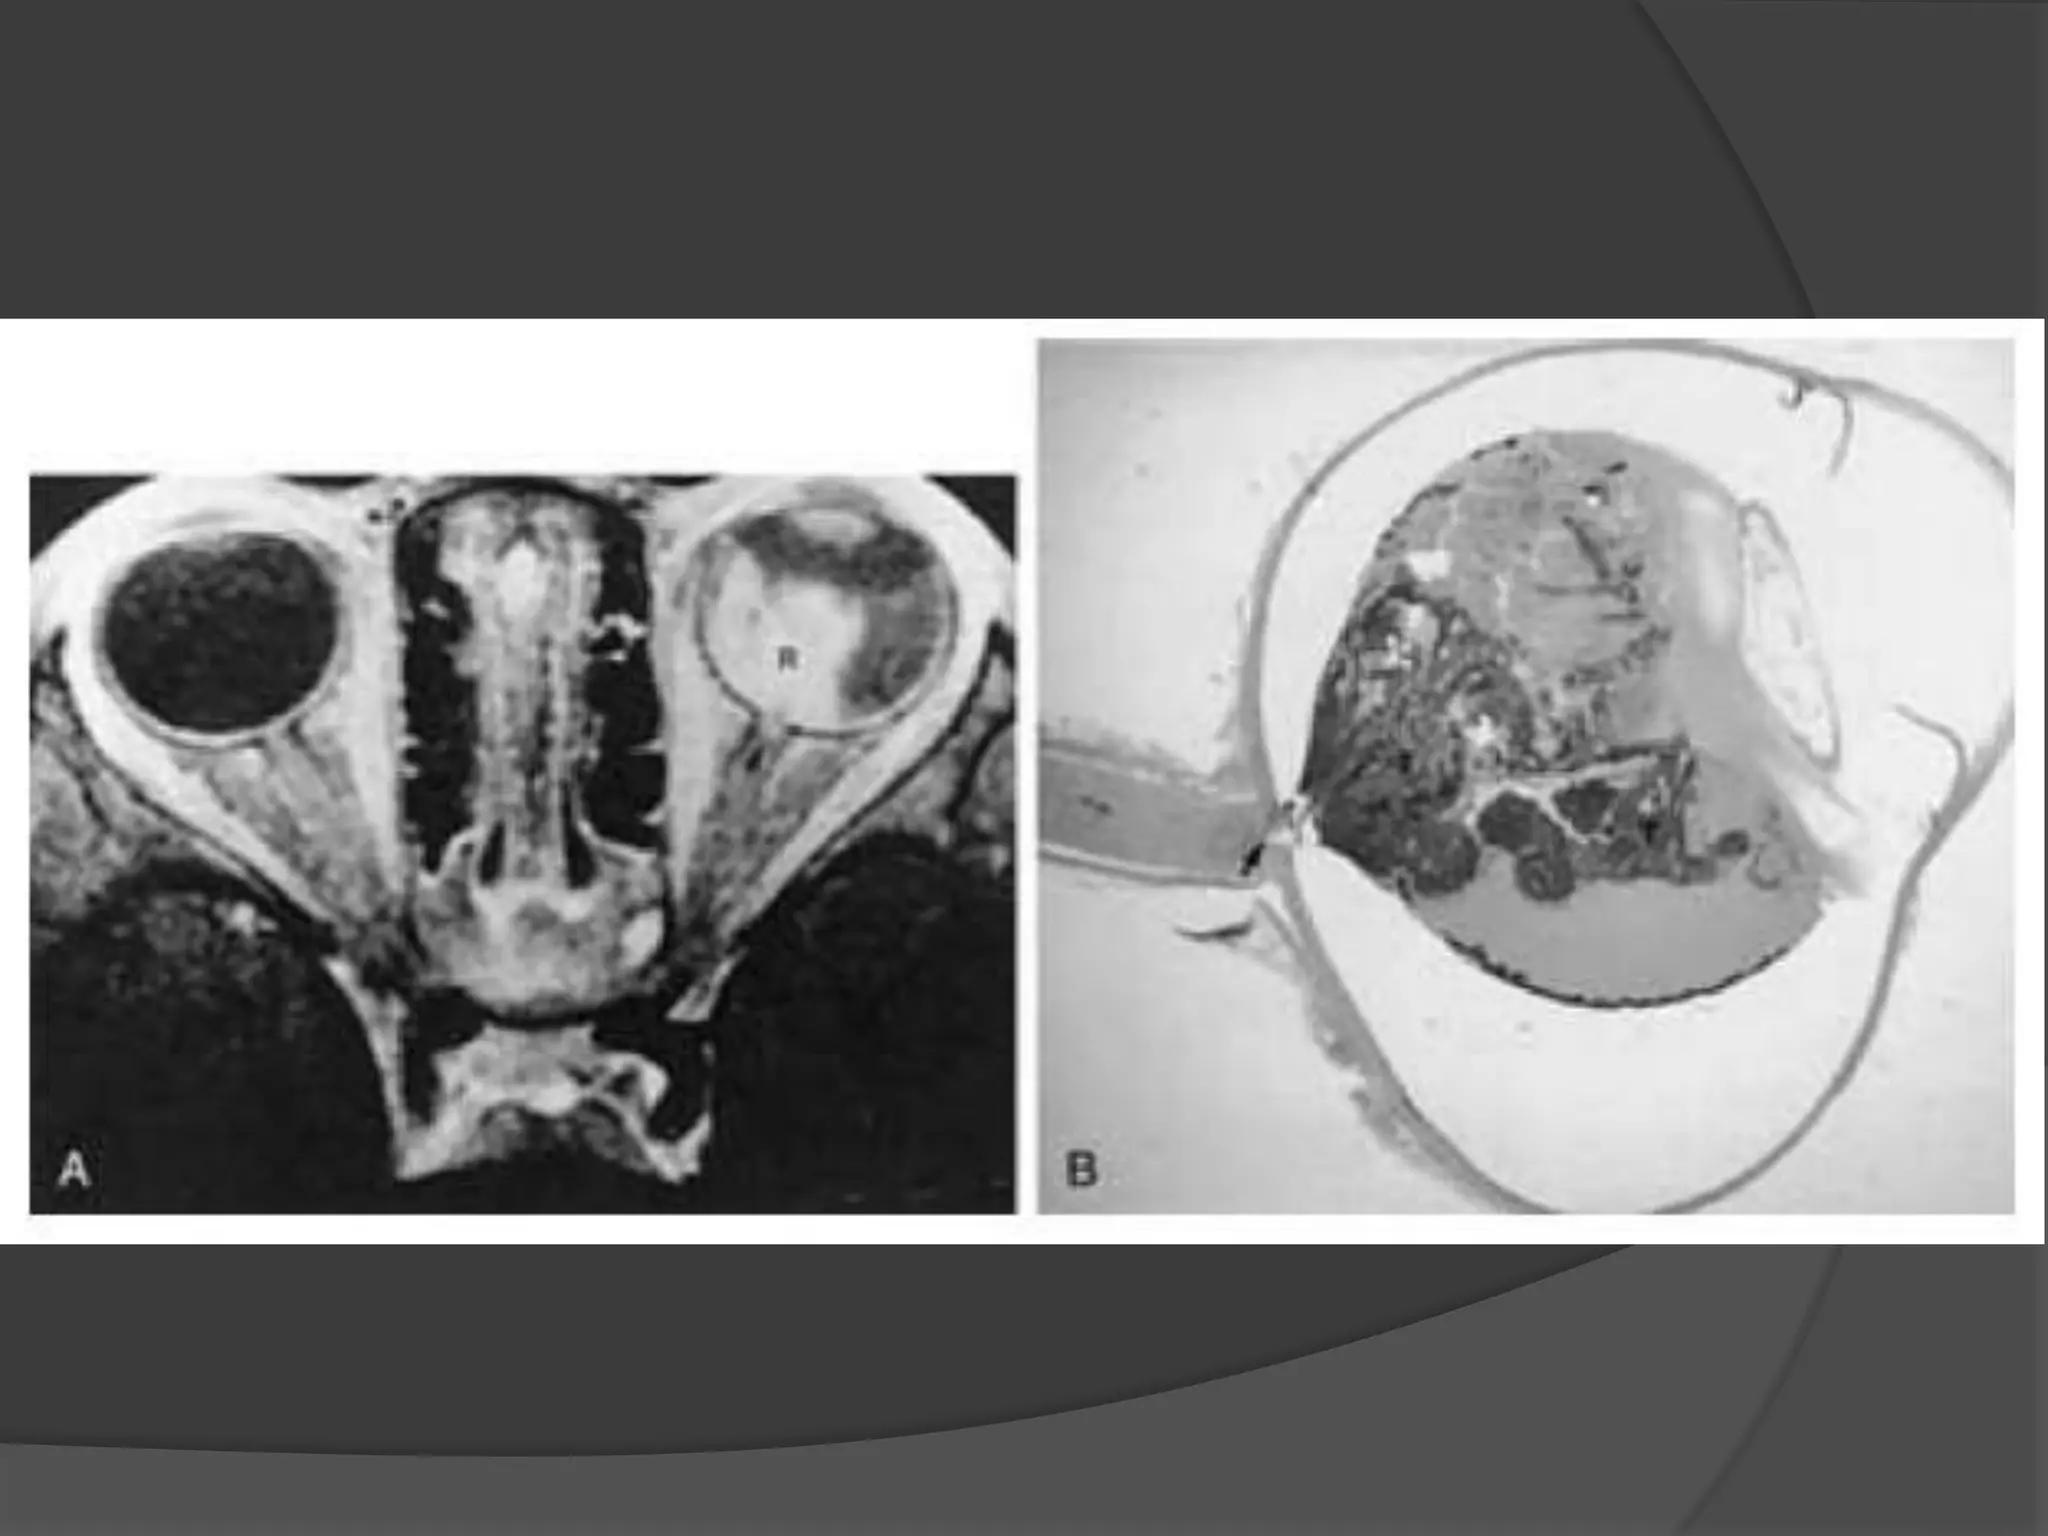

• #46 Malignant melanoma of the choroid. A, Axial CT scan shows a mass (arrow). B, Axial PW MR image (top) and T2-weighted MR image (bottom) show a mass (arrow) and exudative retinal detachment (arrowheads). Retinal detachment is distinguished better on MR imaging than on CT.

• #48 Malignant uveal melanoma. A, Macroscopic section showing a mushroom-shaped melanoma (curved arrows) and a detached retina (open arrows). B, Sagittal PW MR image of another patient shows a hyperintense mass (arrows) and retinal detachment (arrow- head)

• #49 Malignant uveal melanoma. C, Sagittal T2-weighted MR image shows a mushroom-shaped hypointense melanoma (arrows). The subretinal effusion remains hyperintense.